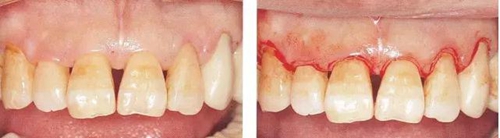

▼圖10-1(左)  術(shù)前狀態(tài)。上頜前牙部有4~7mm的牙周袋。

▼圖10-2(右)  術(shù)前X片。